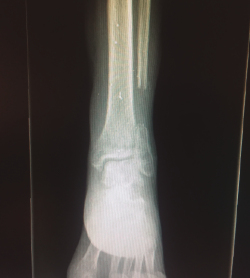

Figura 2. Radiografía tomada en urgencias. Se aprecia fractura del tercio distal del peroné con conminución ósea.

La fractura del peroné se trató de forma conservadora (Figura 4).

Figura 4. Radiografía tomada 5 meses después, tras el tratamiento conservador.